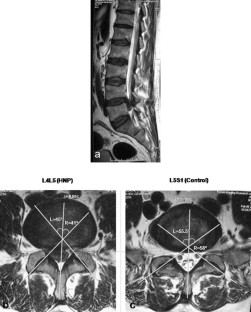

Sixty patients (18–40 years) with single level disc herniation (L3–L4, L4–L5, or L5–S1) were included in the study. Facet angles were measured using MRI of 3-T using the method described by Karacan et al. Facet tropism was defined as difference of 10° in facet joint angles between right and left sides. Normal disc adjacent to the herniated level was used as control. We also examined if disc herniated towards the side of more coronally oriented facet.

Twenty-five herniations were at L4–L5 level and 35 at L5–S1. Statistical analysis was performed using the Fischer Exact Test. At L4–L5 level, 6/25 cases had tropism compared to 3/35 controls (p = 0.145). At L5–S1 level, 13/35 cases had tropism as compared to 1/21 controls (p = 0.0094). Of 19 cases having tropism, the disc had herniated towards the coronally oriented facet in six (p = 0.11).

Fig. 1

Fig. 2